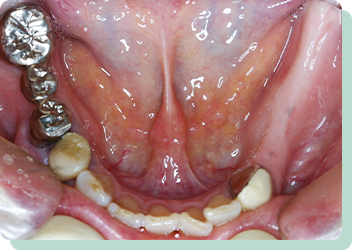

上の歯は残っており、下の歯は全て抜けてしまったケースです。総入れ歯にした場合、受圧加圧のバランスが悪く、何でも噛める入れ歯を作ることは困難です。歯があった時のように食べれるようにという希望でしたが、十分な満足を得ることが出来ました。術後10年以上経過しましたが、問題なく機能しています。

リスク:疼痛・咬合時痛・冷水痛・出血・インプラント手術による歯ぐきなどの損傷・インプラント周囲炎など

費用:インプラントケース総額 2,640,000円